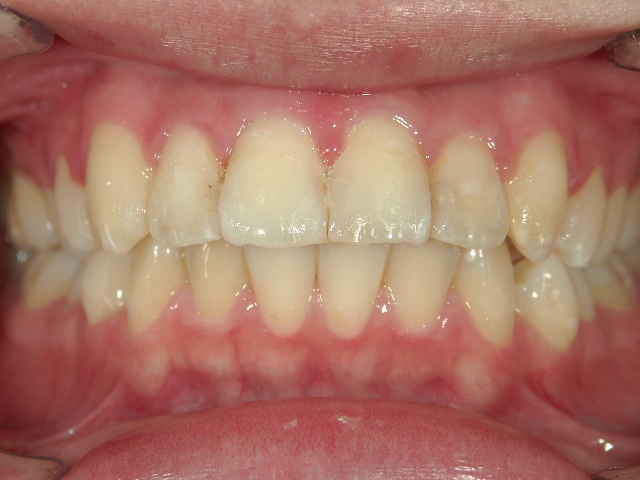

矯正歯科 治療後

no.6_8296_治療後_右.jpgno.6_8296_治療後_正面.jpgno.6_8296_治療後_左.jpg